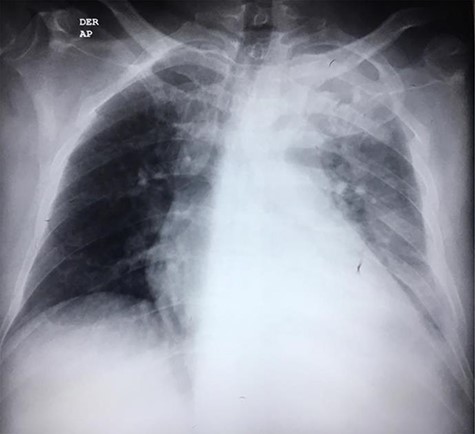

The second case consists of a 47-year-old male from a rural location in Guatemala that presented with malaise, fever, nausea, vomiting and left chest pain, described as oppressive that irradiates toward the neck. The pain got worse while being on supine position. The patient was previously treated with antibiotics and underwent a left thoracostomy due to a chest radiograph that showed a pleural effusion in the lung base (Fig. 3). On chest auscultation and percussion, air entry was reduced and dullness was perceived in the left lung base, respectively. Due to these findings, laboratory tests were ordered. The blood test showed an elevated lactate dehydrogenase at 156 U/L and the pleural fluid analysis showed an elevated lactate dehydrogenase at 1282 U/L, cholesterol level at 66 mg/dl, triglyceride level at 128 mg/dl, presence of Klebsiella pneumoniae and a hematoxylin stain positive for helminth larvae. According to these results, the pleural effusion was classified as an exudate. The high triglyceride level was consistent with a chylous effusion. A chest CT showed left loculated pleural effusion, cardiomegaly, slight pericardial effusion and mediastinal adenomegaly (Fig. 4). The patient presented full recovery after surgical and medical treatment.

In the second case, the patient’s symptomatology, absence of trauma history and his place of residence suggested an infectious etiology. Evidence of a pleural effusion in a chest radiography led to performing a thoracentesis that revealed the presence of a chylothorax, helminth larvae and eosinophils. A chest CT confirmed the absence of malignancy. According to these results, chylothorax most likely developed due to obstruction of the thoracic duct by microfilaria. This diagnosis is also supported by the fact that Guatemala is a tropical country where helminths as Wuchereria bancrofti predominate [7]. The underlying disease was treated with diethylcarbamazine, and the surgical intervention consisted of a pleural toilette through video-assisted thoracoscopic surgery and chylothorax drainage. After these procedures, the patient recovered.